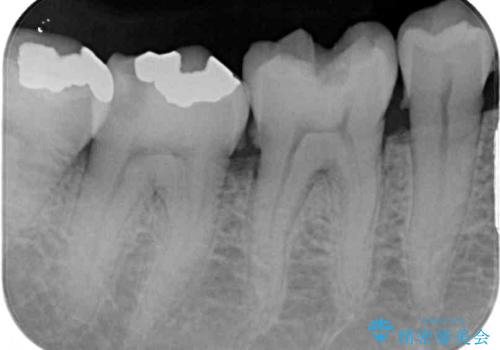

- 銀歯やインレーが外れたまま放置された奥歯の治療を希望して来院された患者様です。

咬合力が著しく強いため、欠損の多い歯はフルジルコニアクラウンへ、その他の虫歯はゴールドインレー(PGAインレー)にて修復することとしました。

来院時は全てセラミックでの治療を希望されていましたが、歯列や咬み合わせから咬合力による破損リスクが高いと判断されたため、ゴールドインレーを選択しました。